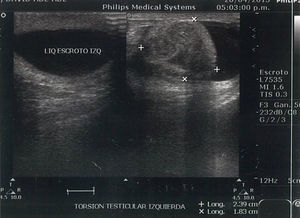

Caso clínicoAcude al servicio de urgencia del Hospital Regional de Alta Especialidad Dr. Gustavo A. Rovirosa Pérez un varón de 15 años de edad, sin antecedentes de importancia. Inició su padecimiento al presentar dolor súbito y continuo en testículo izquierdo, progresivo, con irradiación a la región abdominal e inguinal izquierda, acompañado de náuseas y vómitos, con más de 12 h de evolución a su llegada. En la exploración física, se encontró testículo izquierdo con aumento de volumen en comparación con el contralateral, doloroso, con aumento de la temperatura local, con signo de Prehn positivo, el cual consiste en mejoría del dolor al elevar el testículo afectado, además de ausencia del reflejo cremasteriano (fig. 1).

Los estudios de laboratorio únicamente con leucocitosis. El ultrasonido doppler testicular reportó cambios sugestivos de torsión testicular (figs. 1–3). Se realizó tratamiento quirúrgico de urgencia el mismo día de su admisión. Los hallazgos fueron un testículo izquierdo necrótico, con rotación de 360° del cordón espermático (fig. 4), por lo cual se realizó orquiectomía izquierda. El estudio histopatológico reportó infarto hemorrágico testicular. Durante la convalecencia no presentó complicaciones y fue egresado al día siguiente de su tratamiento quirúrgico.